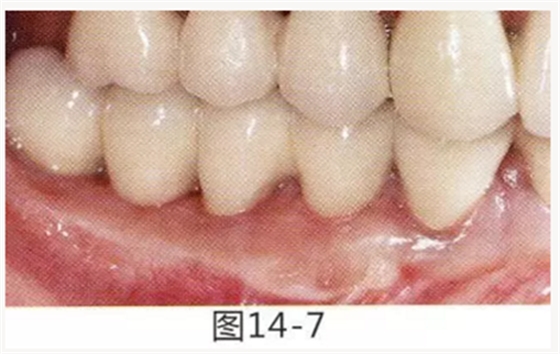

圖14-1 修復(fù)體周圍角化牙齦較少,很難進(jìn)行清潔的狀態(tài),并有緣下齲壞的發(fā)生。

圖14-7 配戴最終修復(fù)體完成5年后的狀態(tài)。保持良好。